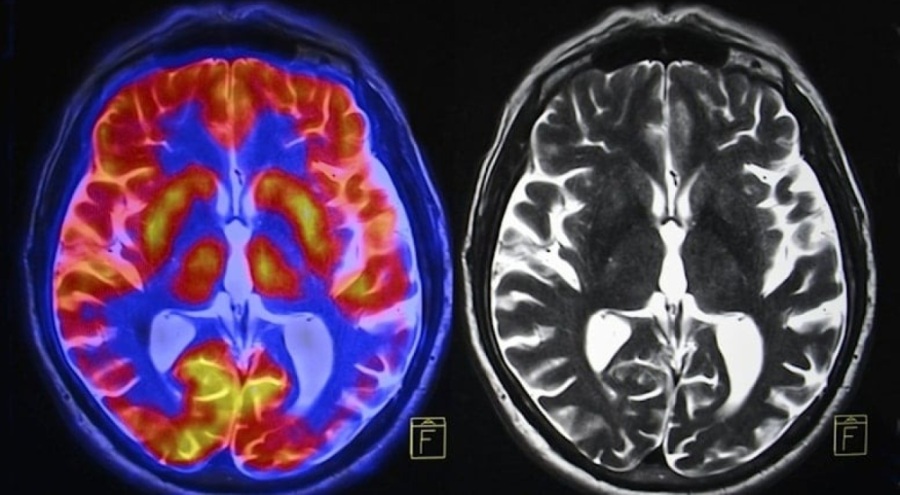

Bilim insanları insan beyninin son 50 yılda küçüldüğünü açıklarken, bazı uyarılarda bulundu.

Beyin sağlığı için beslenmenin öneminin kaçırıldığına dikkat çeken Crawford, beyin sağlığı için yağlı balıkların daha sık tüketilmesi gerektiğinin de altını çizdi. Profesör Crawford, "Modern insan beyni, erken dönem atalarımızın beyinlerine göre yüzde 17 oranında daha küçük" dedi. Çocukların ve onların çocuklarının da geleceğinin risk altında olduğunu belirten Crawford, hamilelerin ve çocuk sahibi kadınların da çocukların emzirilmesi için omega-3 deposu balıkları tercih etmesi gerektiğini söyledi.